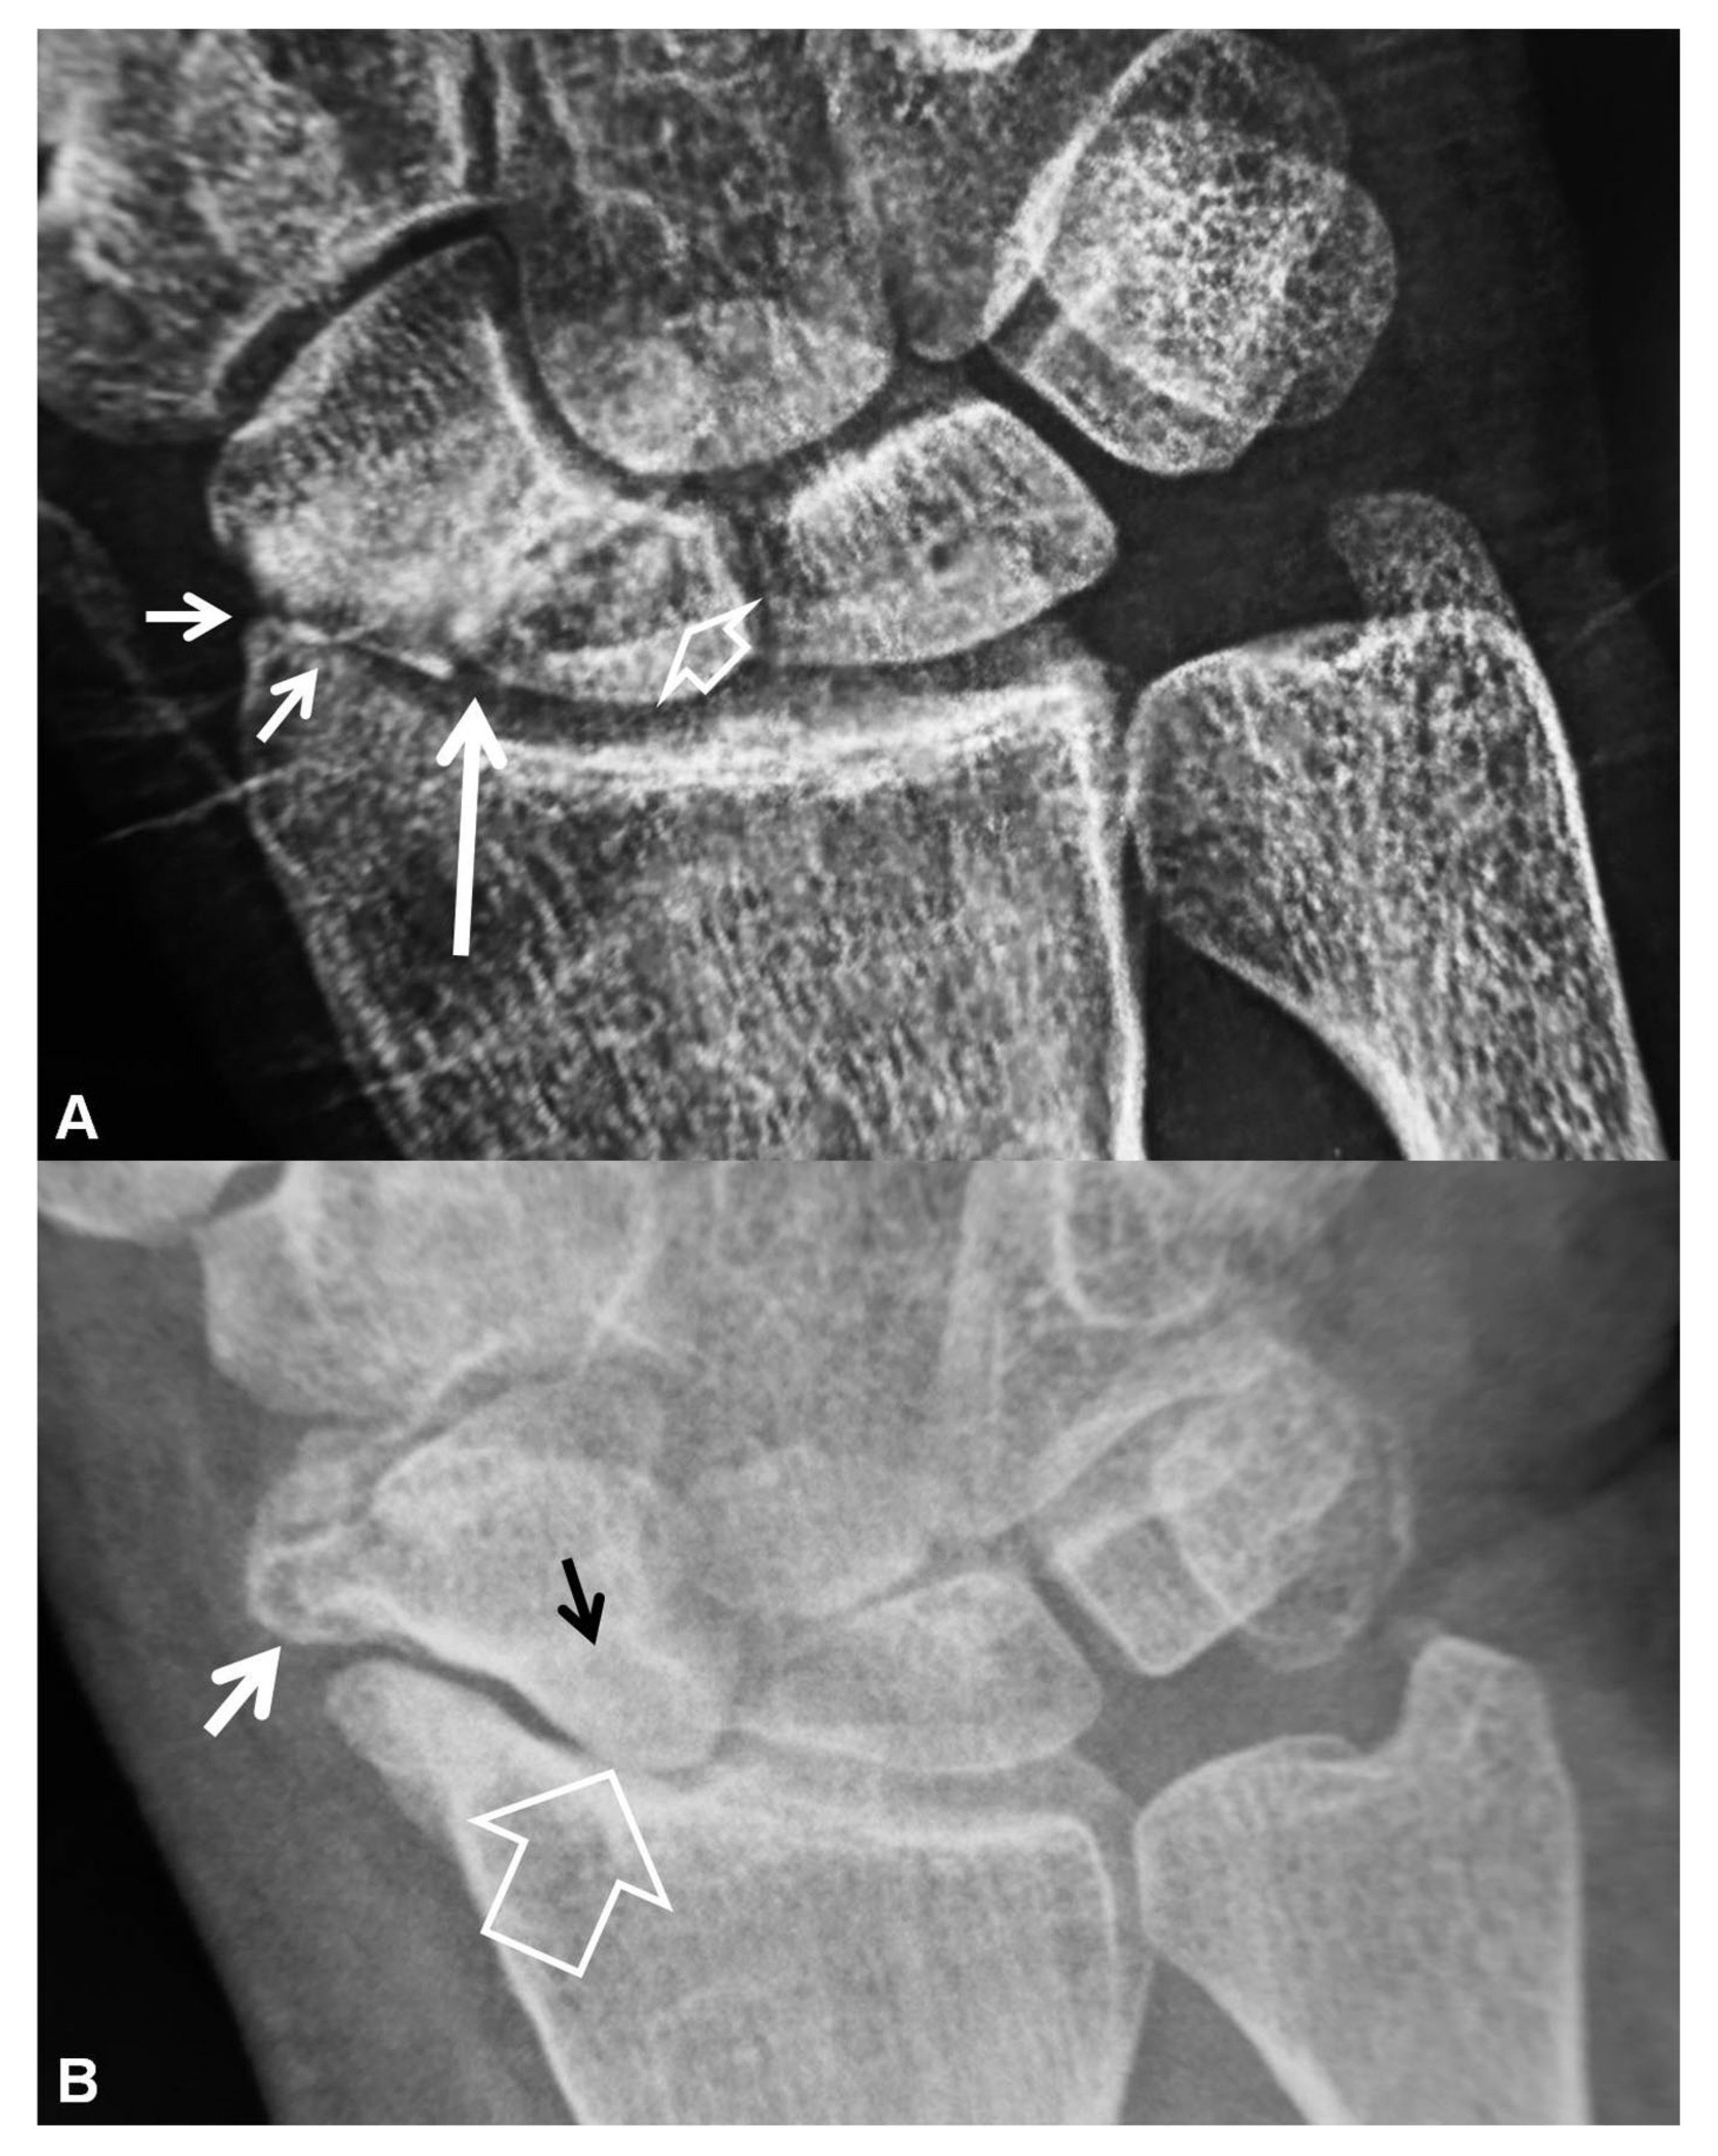

Figure 6.

Coronal (A) and sagittal (B) CT reconstructions of a 23-year-old male patient with an injury 7 years prior to current imaging. SNAC wrist is shown with radioscaphoid joint space narrowing with osteophyte formation (large open arrow left, open arrow right), secondary to proximal pole osteonecrosis (small open arrow left) and pseudarthrosis (thin arrow left). Large cyst formation is shown in the distal pole of the scaphoid (arrowheads).

Figure 7.

A 24-year-old female athlete with a surgically proven scapholunate ligament disruption. PA radiograph (left) image shows scapholunate diastasis (open arrow) and an old fracture of the ulnar styloid (arrowhead). Coronal MDCT arthrographic image (right) shows midcarpal joint opacification (arrowheads) although the SLL looks intact (open arrow). The injection site was distal to the radial styloid (thin arrow). A small dorsal SLL tear was found in the theatre.